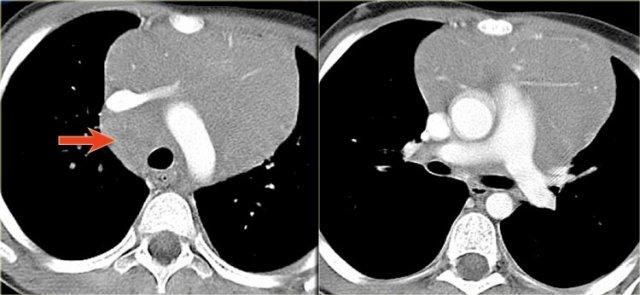

Các hình ảnh cho thấy u tuyến ức ở bên trái và ung thư biểu mô ở bên phải.

Ung thư biểu mô tuyến ức đã xâm lấn tĩnh mạch chủ trên (mũi tên).